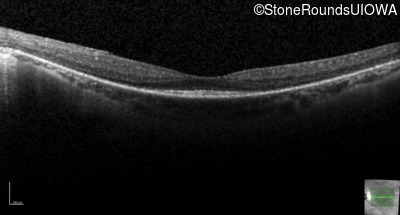

Optical Coherence Tomography - Right - 20/30 +2

Exemplar / OCT Stack